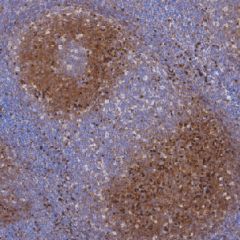

Lambda Light Chain鼠抗人入轻链单克隆抗体

免疫球蛋白分子的基本结构由两条相同的重链Y、u、a、8、)和两条相同的轻链(K或入)组成。任何重链都可与轻链结合,但在免疫球蛋白分子上两条轻链的类型都相同。lg类和亚类之间的K轻链与入轻链的比例不同,在多克降种群中,B细胞的K或入比例约为2:1,单个B细胎表达K或入轻链,决不会两种都表达。大部分K和入链与重链免疫球蛋白结合,但在正常个体中,血清中存在低水平的游离轻链。出现K和入链混台表达的细胞,表明存在多克降种群和B细胞反应性或非肿瘤性增殖

- 阳性部位:胞膜,胞质

- 适用组织:石蜡切片

- 预处理:热修复